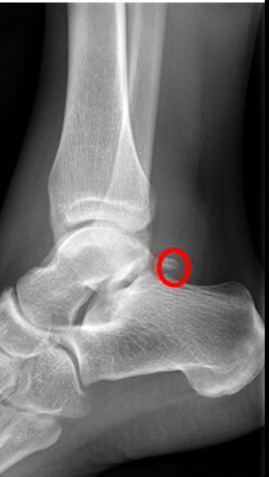

These extra bones represent a portion of a bone that never fused together in growth and development as a child. They form out of basically nothing attaching themselves to existing bone to form a stable area for a tendon to connect to.